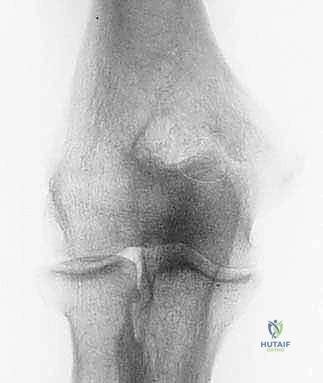

* الأشعة السينية (X-rays): ضرورية جداً لرؤية النتوءات العظمية (Osteophytes) في الناتئ المرفقي، وتضييق مساحة المفصل.

وبشكل محدد، يؤدي هذا الترهل إلى انحشار عظمي مباشر وعنيف بين الجانب الخلفي الإنسي من الناتئ المرفقي (Olecranon) والحفرة المقابلة له في عظم العضد (Olecranon Fossa). هذا الاحتكاك القوي والمتكرر هو أصل المرض، وهو ما يؤدي إلى تفتت الغضروف ونمو زوائد عظمية مؤلمة (Osteophytes) تعيق حركة فرد الكوع تماماً.

يمكن أن يؤدي الانحشار العظمي المزمن، كما هو الحال في متلازمة إجهاد الكوع الانقلابي، إلى إصابات غضروفية كبيرة – أي تلف وتآكل في الغضروف المفصلي الناعم الذي يغطي نهايات العظام – بالإضافة إلى تكوين نتوءات عظمية تفاعلية (Spurs) داخل الجزء الخلفي من المفصل.

وهذا هو السبب في أن سلامة الرباط الجانبي الزندي (UCL) أمر بالغ الأهمية. يتكون هذا الرباط من حزم أمامية وخلفية ومستعرضة، وتعتبر الحزمة الأمامية هي خط الدفاع الأول ضد قوى الانقلاب. عندما يضعف هذا الرباط، تفقد العظام مسارها الصحيح، ويبدأ الناتئ المرفقي (Olecranon) بالاصطدام بجدران الحفرة المرفقية، مما يخلق النتوءات العظمية التي تميز متلازمة إجهاد الكوع الانقلابي.

| فقدان القدرة على الفرد الكامل (Loss of Extension) | عدم القدرة على جعل الذراع مستقيمة تماماً (نقص بمقدار 10 إلى 30 درجة مقارنة بالذراع السليمة) بسبب النتوءات العظمية التي تعمل كحاجز ميكانيكي. | ⭐⭐⭐⭐⭐ |